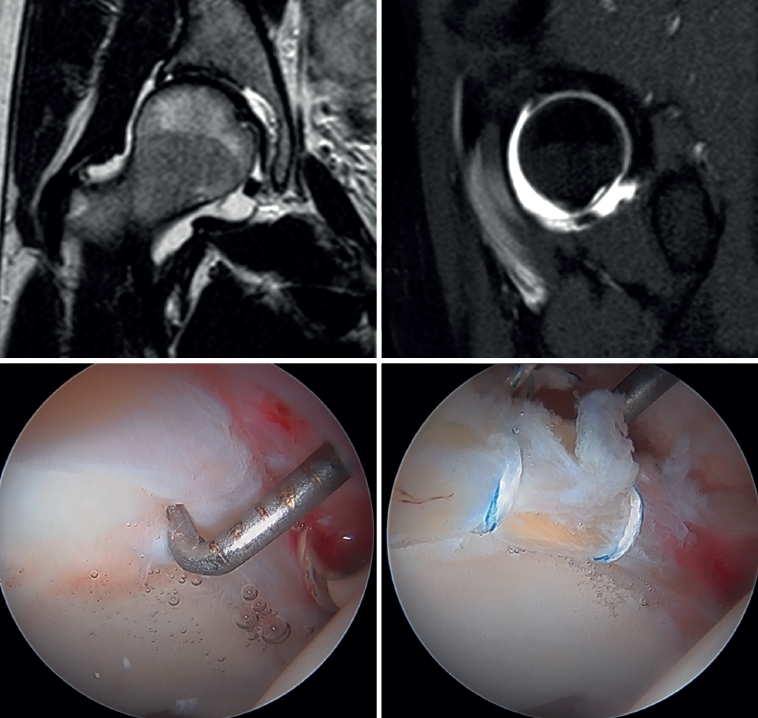

All surgeries were performed in the supine position and on a traction table with perineal post. The anterolateral, mid-anterior and distal anterolateral portals were used. In order to be able to perform the necessary procedures in each patient, an interportal capsulotomy was used in all cases in the central compartment (bony treatment of the acetabular rim, debridement of chondral lesions to secure stable edges, microfractures, labral debridement or repair), except in young women with signs of joint hyperlaxity, in which case independent capsulotomies were used (Figure 1). In patients with cam-type deformities (alpha angle >55°), a T-capsulotomy (with different edge traction systems, and only in those patients with difficult access to the femoral bump) was performed to gain access to the peripheral compartment and resect the femoral deformity until an adequate head-neck transition was achieved to prevent conflicts of space, tested by intraoperative dynamic examination to confirm adequate correction (Figure 2). The intraoperative procedures made are described in Table 1.